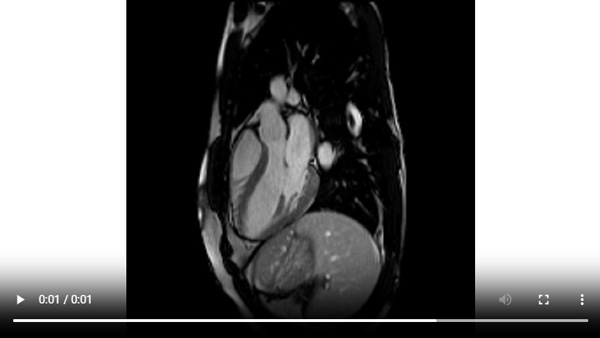

Figure 1A : Séquence Ciné-IRM - Coupes petit-axe basal

Figure 1B : Séquence Ciné-IRM - Coupes petit-axe médian

Figure 1C : Séquence Ciné-IRM - Coupes petit-axe apical

Figure 1D : Séquence Ciné-IRM - Coupes 2-cavités

Figure 1E : Séquence Ciné-IRM - Coupes 3-cavités

Figure 1F : Séquence Ciné-IRM - Coupes 4-cavités